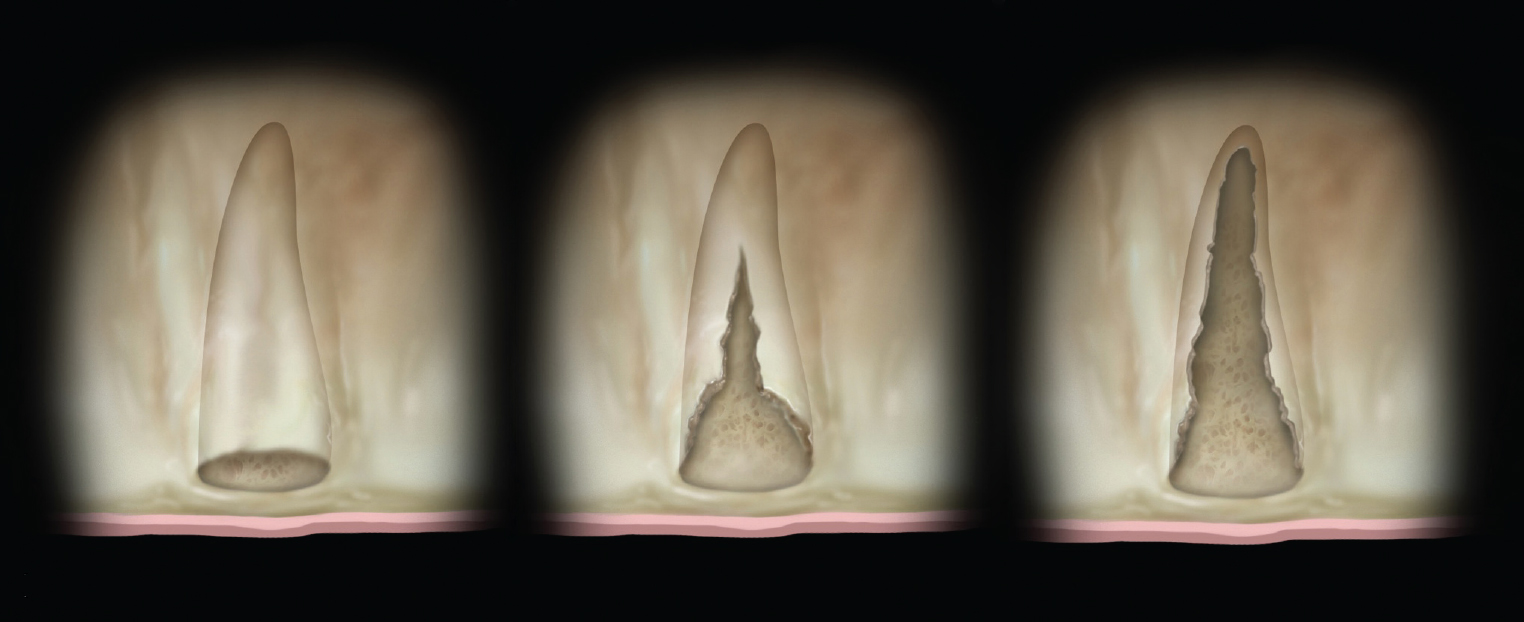

The shape and amount of bone present apical to the extraction socket is the apical topography and is important in treatment planning for both immediate and delayed implant placement. For immediate implant placement, the apical topography is significant, as 3 mm to 4 mm of native bone needs to be engaged for primary stability of the implant.1,2 If planning a 2-stage approach with site preservation and delayed implant placement, analysis of the apical topography is also essential. If a tooth with an apical concavity is extracted and a graft is placed only inside the socket, there may not be adequate bone following healing to place the implant in the proper position without additional surgical procedures3 (Figure 2). Teeth that do not have enough apical bone to provide the housing necessary for immediate implant placement or delayed implant placement with grafting inside the socket alone are defined as having inadequate apical topography. This inadequacy can be the result of periapical pathologies or the anatomy of the alveolus.

Imagery depicting examples of single-rooted sockets showing periodontium status, socket conditions, and CBCT imaging is presented in Figure 2 through Figure 5.

Grade I sockets are the most ideal. Following tooth extraction, a socket that has an intact buccal plate, adequate interproximal bone, and satisfactory apical topography will fall into this category. In this classification, an intact buccal plate is defined as having no fissures or dehiscences and less than 25% loss of height (Figure 4, left; Figure 5, left). This percentage of buccal plate loss was selected as the cutoff based on the average root length of single-rooted teeth, which is 14.2 mm,25 and the amount of buccal plate that can be reliably regenerated during immediate implant placement. Adequate apical topography is defined as enough bone present apical to the extraction site to allow for engagement of 3 mm to 4 mm of a properly positioned immediate dental implant (Figure 2).1,2 Adequate interproximal bone is defined as no or mild (up to 2 mm) periodontal bone loss on the adjacent teeth as to allow for support of the interproximal soft tissue and to enable placement of the platform of an immediate implant in the proper apical-coronal position relative to the adjacent teeth while still being bordered by bony walls on the mesial and distal aspects26 (Figure 3, left).

Grade II sockets are differentiated from Grade I by the amount and quality of the remaining buccal plate. A Grade II socket has a fissure, dehiscence, or deficiency of the buccal plate totaling a 25% to 50% loss. Like Grade I sockets, they have adequate interproximal bone and apical topography (Figure 3, left; Figure 4, center; Figure 5, center).

Grade III sockets are the most deficient and include any socket with inadequate apical topography, insufficient interproximal bone, or more than 50% loss of buccal plate. Inadequate apical topography is defined as not enough bone present apical to the extraction site to allow for implant placement and may be the result of bone loss caused by periapical lesions or concavities due to existing anatomy of the alveolus (Figure 4, right; Figure 5, right). Insufficient interproximal bone is defined as moderate-to-severe periodontal bone loss—greater than 2 mm on one or both of the adjacent teeth.